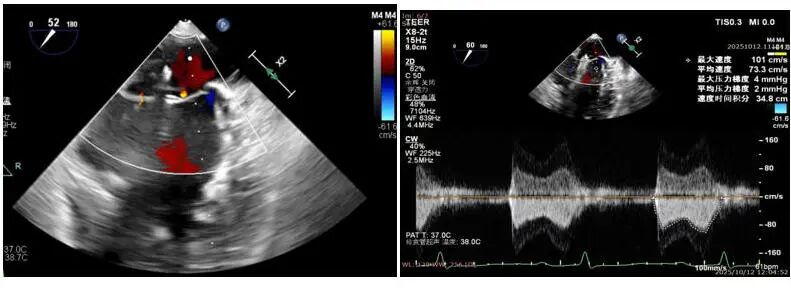

患者女性,72岁,反复心悸、胸闷多年,既往曾在外院接受房颤射频消融,但术后再次复发。入院后检查发现:房颤合并中重度二尖瓣反流,且瓣口面积仅4.3cm²,病情复杂、风险极高。经多学科团队联合评估,本次手术中,团队通过三维标测系统精准定位心律失常触发点,并以脉冲消融完成心房电活动重构。消融后心律即刻恢复窦性节律,体现了PFA在病例中快速、精准、微创的独特优势。与传统射频消融相比,脉冲消融显著减少肺静脉狭窄及食管损伤风险,术后房颤复发率更低,为房颤患者提供了更优的治疗方案。针对患者的中重度二尖瓣反流,手术团队在精准经食道超声导航下完成TEER瓣膜修复。瓣叶精准对合后,反流明显减少,跨瓣压差维持在理想水平,术后心功能显著改善。

术前患者二尖瓣反流中重度,二尖瓣后叶栓系,反流主要集中在2区,累及部分1区和3区,瓣口面积仅有4.3cm²

在瓣口面积偏小仅有4.3cm²的情况下,决定术中在2区植入一枚SW0609型号DragonFly™二尖瓣夹解决反流问题,术中用到DragonFly™二尖瓣夹前后瓣叶独立捕获功能,实现了对病变瓣叶的精准定位与捕获。术中房间隔穿刺高度3.8cm,夹闭后L侧微量反流,释放后反流未明显增加,跨瓣压差2mmHg